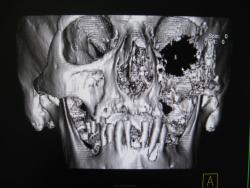

Вот такое безобразие выросло у человека. Когда он обратился образвоание было вероятно меньше к сожалению снимков нет. Лучевая терапия оказалась неэффективной как видите.

Каюсь гистологию даже не смотрел засмотрелся на картинку. Да изначально была гайморова пазуха. Затем после лучевой терапии на фоне ухудшения решили сделать КТ благо сейчас появилась такая возможность. И вот прорастание в глазницу с разрушение нижней её стенки, в носовую, ротовую полости, в среднюю черепную ямку. В общем все бесполезно...